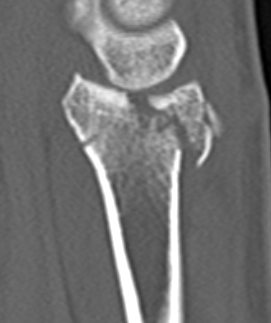

CT for further evaluation of articular congruency

1. Distal radial Step > 2mm

2. Articular incongruency sigmoid notch / DRUJ > 2 mm